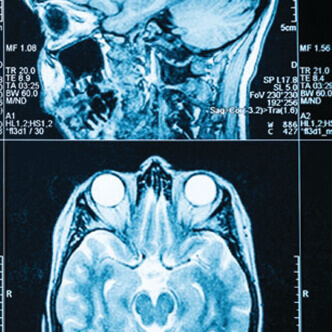

Examenul neurologic include diverse probe: de pareză, de sensibilitate (tactilă superficială și profundă, termică și dureroasă), de coordonare, examenul limbajului și al memoriei, statusul mental și reflexele. Cu ajutorul acestei examinări, neurologul își poata da seama dacă un pacient are un deficit motor sau de sensibilitate, tulburare de vedere, de limbaj sau de memorie. Totodată, acest tip de examinare ajută la localizarea – uneori destul de precisă – a unei leziuni. În funcţie de problema neurologică, tratamentul poate include trimiterea pacientului către un fizioterapeut, prescrierea de medicamente sau recomandarea unei proceduri chirurgicale.

- 2008 - 2011 - medic colaborator Medinst, centru privat de neuroimagistica, proiect de cercetare in imagistica volumetrica cerebrala. Participare la primul RMN de perfuzie in AVC-ul acut din Romania